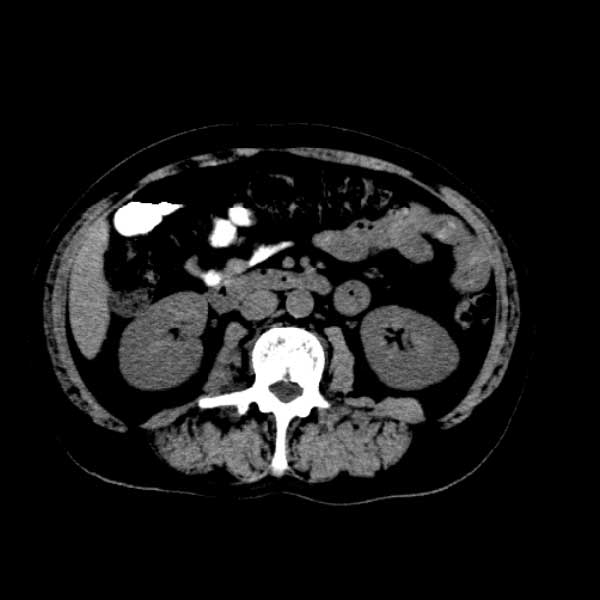

标题: CT13513:男 71 腹部疼痛20余天,近几天高热就诊,骨窗未见异 [打印本页]

标题: CT13513:男 71 腹部疼痛20余天,近几天高热就诊,骨窗未见异

考虑感染性病变可能性大,起源于阑尾?

感染,脓肿形成

考虑为化脓性阑尾炎.脓肿形成.及多肌肉累及.

考虑右侧腰大肌脓肿,向右髂窝、右腹股沟流注。

支持化脓性阑尾炎伴右髂窝脓肿、腰大肌腰方肌脓肿形成。

首先考虑化脓性阑尾炎伴腰大肌、腰方肌脓肿,不除外回盲部结核。

回盲部癌待排除。

患者肠镜检查考虑结肠癌,病理证实

患者肠镜检查考虑结肠癌,病理证实。肺部ct可见多发结节,考虑转移